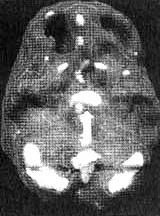

Мозг Эллен — последствия инсульта ![]() Трехмерное изображение поверхности мозга, вид слева. Обратите внимание на обширную «дыру», сформировавшуюся в результате инсульта в левой лобной доле 2. SPECT позволяет дать точную оценку состояния пациента, позволяющую предотвратить, заболевание в будущем. Нэнси, 59 лет, страдала от тяжелой депрессии, не поддававшейся лечению. Поступила в психиатрическую лечебницу, где ей было проведено исследование SРЕСТ. Каково же было мое удивление, когда оказалось, что в прошлом, при полном отсутствии соответствующих симптомов, она перенесла два обширных инсульта. Таким образом, стало понятно, что вызвало эту депрессию, не поддававшуюся обычному лечению. У 60 % пациентов, перенесших кровоизлияние во фронтальных долях, через год развивается тяжелая депрессия. Получив результаты SPECT, я немедленно проконсультировался с неврологом, который постарался определить причины инсультов, к которым нередко приводят, скажем, бляшки в сонных артериях или сердечная аритмия. Он пришел к выводу, что причиной инсультов у Нэнси стали тромбы, и назначил ей препараты, снижающие вязкость крови, чтобы предотвратить развитие новых инсультов. Мозг Нэнси — последствия двух инсультов ![]() Трехмерное изображение поверхности, вид сверху ![]() Трехмерное изображение поверхности, вид справа 3. С помощью SPECT можно получить информацию, помогающую врачу добиться понимания и сострадания к пациенту у членов его семьи. Фрэнк — состоятельный, хорошо образованный человек. Вскоре после того как ему исполнилось 70 лет, он стал забывчивым. Сначала он забывал мелочи, но со временем провалы в памяти стали прогрессировать, и он начал забывать значимые факты собственной биографии: где он живет, как зовут его жену и даже как зовут его самого. Жена и дети были не в состоянии понять, чем вызваны такие перемены, а его рассеянность и забывчивость их нередко раздражали. Результаты SPECT показали, что у Фрэнка на всей поверхности мозга отмечается резкое снижение активности, и особенно во фронтальных, париетальных и височных долях. Это была классическая картина синдрома Альцгеймера. Показав семье снимки и объяснив, что забывчивость Фрэнка имеет четкую физиологическую природу, я помог им осознать, что он не специально раздражает их, а серьезно болен. Впоследствии, вместо того чтобы упрекать его за забывчивость, близкие Фрэнка стали поддерживать его и разработали схемы, позволившие эффективнее бороться с трудностями, возникающими у всякого, кто вынужден жить рядом с человеком, страдающим болезнью Альцгеймера. Мозг Фрэнка — болезнь Альцгеймера ![]() Трехмерное изображение поверхности, вид сверху ![]() Трехмерное изображение нижней поверхности Обратите внимание на выраженное общее снижение активности, особенно в париетальных долях (см. стрелки, рис. слева) и в височных долях (см. стрелки, рис. справа). 4. SPECT позволяет проводить дифференциальную диагностику состояний со сходной симптоматикой. Я познакомился с Маргарет, когда ей было 68. Выглядела она неухоженно и неопрятно. Маргарет жила одна, и ее близких это очень беспокоило, так как у нее появились симптомы тяжелой деменции. После того как она чуть не сожгла дом, оставив включенной плиту, ее поместили в психиатрическую клинику, где в то время работал я. Из общения с ее близкими обнаружилось, что Маргарет часто забывала, как зовут ее собственных детей, и нередко, ведя машину, сбивалась с дороги и оказывалась в незнакомом месте. Водительские навыки ухудшились настолько, что после четырех небольших ДТП всёго за шесть месяцев у нее отобрали права. К тому времени, когда я встретился с ее близкими, многих из них эта ситуация уже утомила, и они были готовы сдать Маргарет в специализированный приют. Другие были против такого решения и хотели бы сначала обследовать ее в условиях стационара. На первый взгляд казалось, что Маргарет страдает болезнью Альцгеймера. Однако по результатам SPECT обнаружилось, что активность мозга в париетальных и височных долях не нарушена. Если бы у нее был синдром Альцгеймера, кровоток в этих областях должен был бы быть снижен. Вместо этого единственной патологией, которую нам удалось обнаружить на снимках SPECT, стала зона повышенной активности в глубокой лимбической области в центре мозга. Такая картина часто наблюдается у пациентов, страдающих депрессией. Из-за схожей симптоматики у больных старшего возраста нередко бывает трудно дифференцировать депрессию и болезнь Альцгеймера. Тем не менее при псевдодеменции (депрессии, которая выглядит как слабоумие) человек может выглядеть слабоумным, на самом деле таковым не являясь. Это чрезвычайно важный момент, так как, диагностировав болезнь Альцгеймера, мы даем близким ряд специальных рекомендаций и назначаем пациенту некоторые медикаментозные средства. Между тем, диагностируя депрессию, мы проводим агрессивную медикаментозную терапию антидепрессантами в сочетании с психотерапией. Результаты обследования Маргарет убедили меня в том, что ей следует назначить антидепрессант Wellbutrin (бупропион). Всего три недели спустя она уже была разговорчивой, ухоженной и охотно общалась с другими пациентами. Через месяц после госпитализации ее выписали домой. Перед выпиской она попросила меня написать письмо в автоинспекцию с просьбой вернуть ей водительские права. Поскольку мы с ней ездим по одному и тому же шоссе, я заколебался. Я сказал ей, что, если улучшение будет стойким и сохранится на протяжении по меньшей мере полугода, а сама она станет придерживаться рекомендаций врача и принимать все лекарства, я напишу письмо в автоинспекцию. Через полгода она оставалась в хорошей форме. Я сделал повторный SPECT — результаты показали полную норму. Тогда я обратился в автоинспекцию, и ей вернули права. Мозг Маргарет — псевдодеменция ![]() Трехмерное изображение снизу — активный мозг, до лечения. ![]() Трехмерное изображение снизу активный мозг, после лечения. |